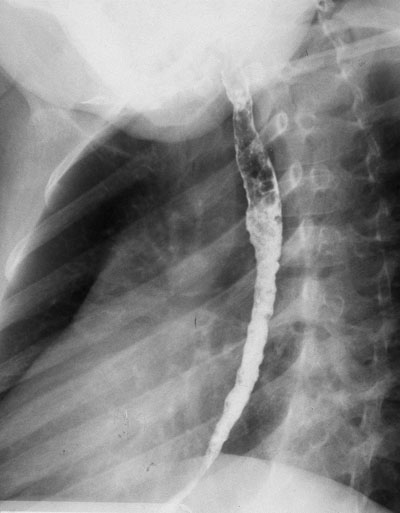

Выраженный стеноз пищевода на ФЭГС

Стриктура пищевода - сужение пищевода, часто вызванное воздействием кислотного содержимого желудка, забрасываемого в пищевод.

Основным симптомом стриктуры пищевода является дисфагия, которая нередко сочетается с изжогой, кислой и горькой отрыжкой. Быстро прогрессирующая дисфагия (менее 3 мес) с потерей массы тела более характерна для рака пищевода.

С целью уточнения диагноза первоначально проводится исследование грудной клетки и пищевода, далее - эзофаго-гастроскопия.

На основании эндоскопической картины по выраженности сужения пищевода выделяют 4 степени и столько же по клинике синдрома дисфалгии (0 - нормальное глотание; 1 - периодические затруднения при прохождении твердой пиши; 2 - питание полужидкой пищей: 3 - питание только жидкой пищей; 4 - невозможность проглотить слюну). При этом учитывают также протяженность рубцового стеноза пищевода, так как от этого нередко зависит успешность неоперативного расширения стриктуры и адекватного восстаноатения перо-рального питания.